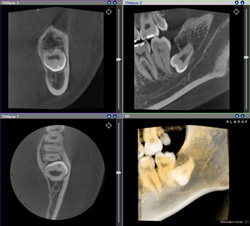

CTを用いた診断の最大のメリットは、精度の高い検査ができ正確な診断ができることです。正確に診断することで治療に伴うリスクが避けられるので、患者さまに少ない負担での治療が可能になります。通常はレントゲンで診断ができないと大学病院に紹介しなければなりませんが、CT検査が可能な当院ではそのような煩わしさがなくなり、より質の高い歯科医療の提供が実現します。